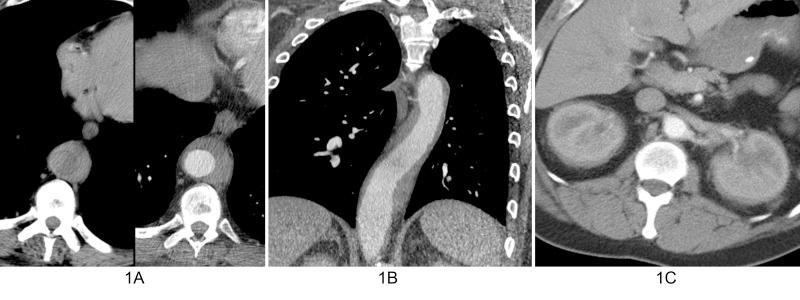

Erdheim-Chester disease (ECD) is a rare multisystemic non-Langerhans cell histiocytosis that may be clonal and inflammatory in origin. The hallmark of the disease is infiltration of various organ systems by CD68+/CD1a- histiocytes containing foamy lipid-laden inclusions. The manifestations and course of the disease are variable and depend on the organ systems that are affected. Patients may be asymptomatic or may develop life-threatening complications, including myocardial infarction. The most common clinical manifestation is lower extremity bone pain. Imaging manifestations of the disease include symmetric osteosclerosis of the distal long bones, circumferentially "coated" aorta, pleural and pericardial thickening/fluid, and perirenal encasement. Treatment for the disease is evolving, particularly with the use of molecular BRAF inhibition. We present a case of a patient with ECD initially suspected based on the imaging manifestations.

厄德里希-切斯特病(ECD)是一种罕见的多系统非朗格汉斯细胞组织细胞增多症,其起源可能是克隆性和炎症性的。该疾病的标志是含有泡沫状脂质包涵体的CD68+/CD1a-组织细胞浸润各种器官系统。疾病的表现和病程各不相同,取决于受影响的器官系统。患者可能无症状,也可能出现危及生命的并发症,包括心肌梗死。最常见的临床表现是下肢骨痛。该疾病的影像学表现包括远端长骨的对称性骨硬化、主动脉周围“包绕”、胸膜和心包增厚/积液以及肾周包裹。针对该疾病的治疗正在不断发展,尤其是使用分子BRAF抑制剂。我们报告一例最初根据影像学表现怀疑为ECD的患者病例。